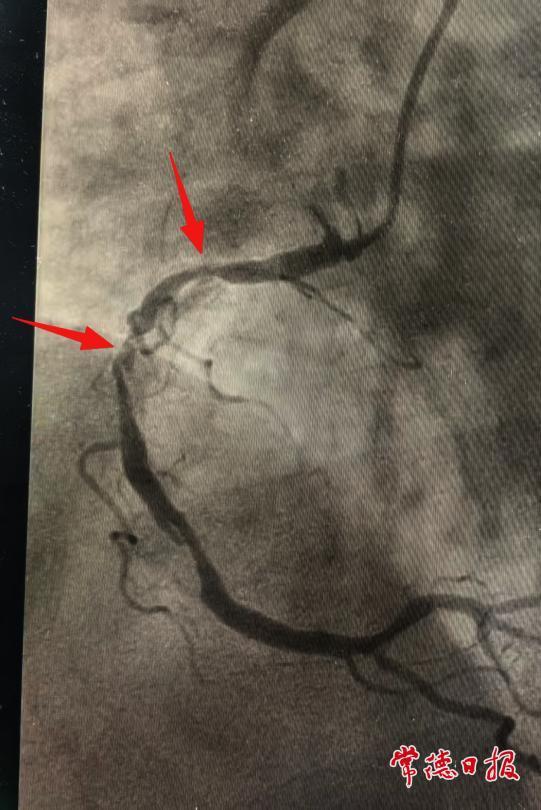

120急救人员到达现场后,将苏醒的陈老快速转运至常德市第一中医医院。经检查确诊为急性心肌梗死,心血管科二病区介入团队立即为其实施急诊介入手术,置入支架2枚,术后患者病情逐步稳定。